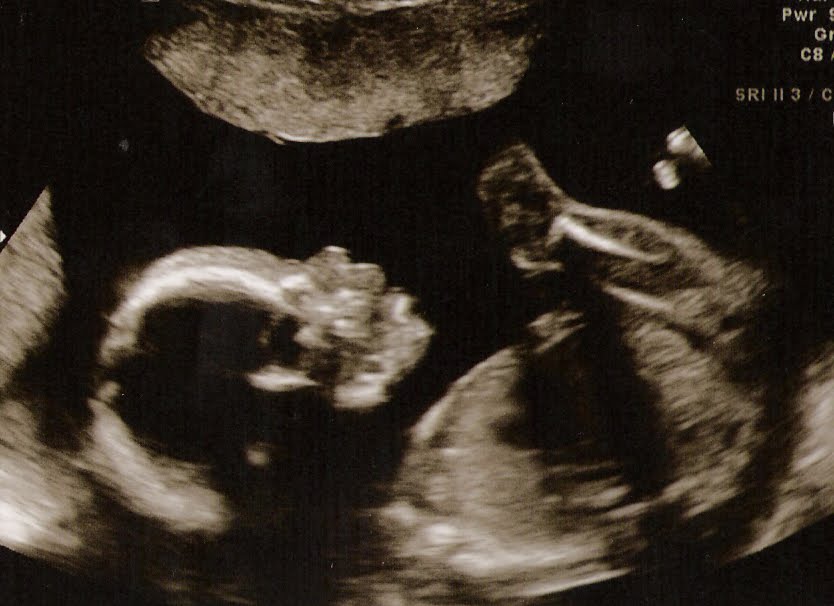

Words do not express how we felt as we watched our baby on the screen at our ultrasound today. Our baby girl is perfect and healthy and beautiful. She weighs 15 oz now and was “talking” to us by opening and closing her mouth for most of the ultrasound. We can’t wait to welcome Haley Lynn into our family in September.

We got some great video but the files are too big to convert so I can’t upload them. We also saw some 3-D images, which was unexpected.